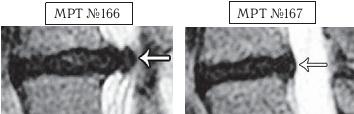

На МРТ № 166 (увеличенный фрагмент МРТ № 164) наблюдается помимо секвестрированной грыжи межпозвонкового диска также и спондилёз, то есть хроническое дегенеративно-дистрофическое заболевание позвоночника (формирование костных выростов по краям тел позвонков), что говорит о длительности заболевания и наличии в прошлом (до лечения вытяжением) протрузии. Эти факты свидетельствуют о прямых противопоказаниях к вытяжению позвоночника.

На МРТ № 167 (увеличенный фрагмент МРТ № 165) наблюдается состояние межпозвонкового диска после лечения методом вертеброревитологии. «Клиновидность» межпозвонкового диска устранена в связи с восстановлением биомеханики позвоночника. Оставшийся спондилёз — костный нарост, образовавшийся вследствие «включения» компенсаторных механизмов над выпятившимся межпозвонковым диском, к сожалению, обратного развития не имеет. Однако это «не мешает жить», поскольку главная причина, спровоцировавшая нарушение функций позвоночника и, соответственно, нестерпимые боли у пациента (секвестрированная грыжа диска, вызвавшая абсолютный стеноз спинномозгового канала), была устранена методом вертеброревитологии.